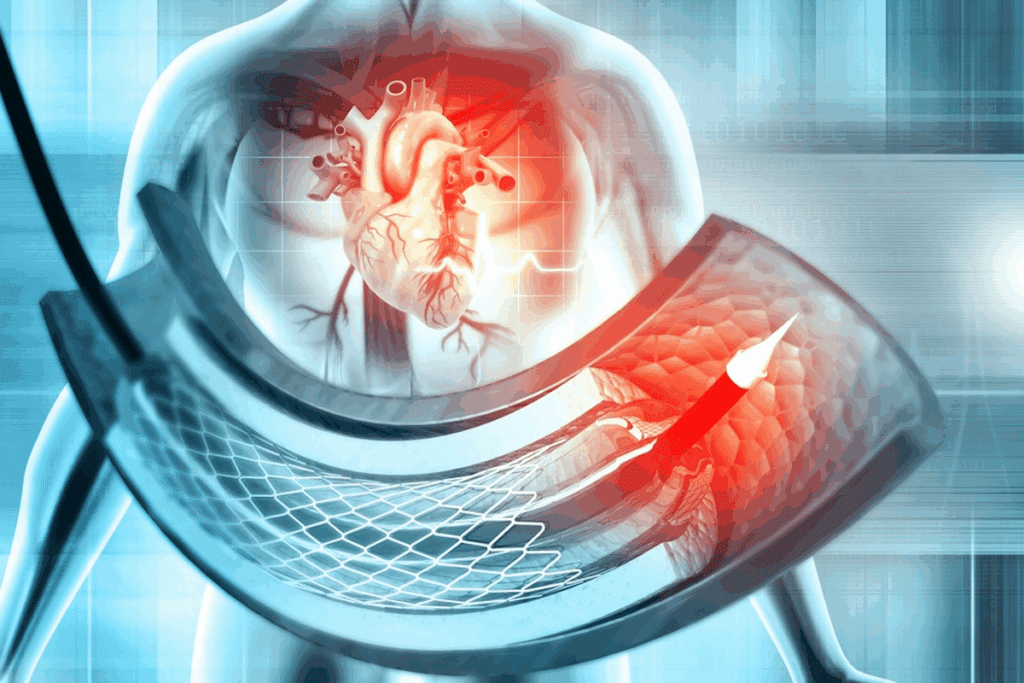

Coronary vessel imaging has changed cardiology a lot. It helps doctors diagnose and treat heart issues better. This imaging is key to understanding heart vessel structure and function. It’s vital for managing heart disease.

Coronary angiography lets doctors see the heart’s arteries. It uses a contrast agent to spot blockages. Coronary artery photos from this help plan treatments.

A top cardiologist says, “Coronary angiography is the best way to find heart disease. It gives clear images for treatment.”

“Seeing heart arteries live has changed how we treat heart disease,” said Medical Expert, a famous cardiologist.

| Imaging Technique | Description | Advantages |

| Coronary Angiography | Involves injecting contrast agent into coronary arteries | Provides detailed images of coronary arteries, guides interventions |

| CT Coronary Angiography | Non-invasive imaging using CT scans | Less invasive, useful for assessing plaque burden |

Coronary circulation diagrams are key for understanding heart vessel anatomy. They come from advanced scans like CT or MRI. These diagrams help doctors plan treatments.

Advanced imaging, like coronary circulation diagrams, has made diagnosis better. These tools help doctors create treatment plans that fit each patient’s needs.

We use these advanced imaging methods for full patient care. By combining coronary artery photos and angiography with detailed diagrams, we make accurate diagnoses and effective treatments.